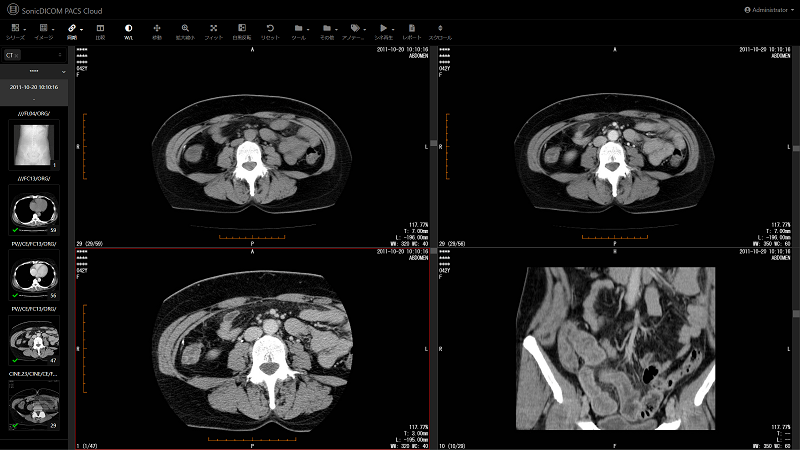

本サービスは、CTやMRIなどの検査装置で撮影した医用画像をクラウド上で管理し、インターネットに接続できるパソコンやタブレット端末があれば、場所を選ばず画像を参照することができるサービスです。専用ビューアのインストールが不要で、Webブラウザ(Google Chrome、Mozilla Firefox、Microsoft Edge等)から簡単に医用画像を参照することができます。またビューアは10ヵ国語に対応しており、データの保管先も世界6ヵ国7リージョンからユーザー自身で選択することができます。